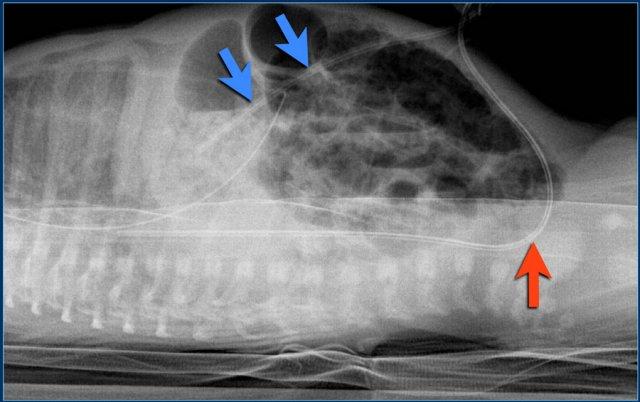

Các phát hiện bao gồm:

- Đây là phim chụp X-quang tư thế nằm nghiêng với chùm tia ngang.

Hình ảnh minh họa đường truyền tĩnh mạch rốn đi theo đường đi của tĩnh mạch rốn vào trong gan (mũi tên xanh).

Đường truyền chưa đủ sâu. - Đường truyền động mạch rốn đầu tiên đi xuống phía dưới và vào động mạch chậu (mũi tên đỏ).